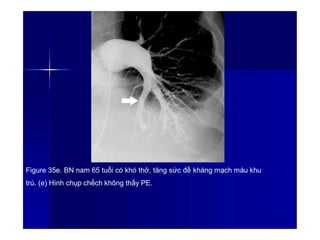

Figure 35e. BN nam 65 tuổi có khó thở, tăng sức đề kháng mạch máu khu

trú. (e) Hình chụp chếch không thấy PE.